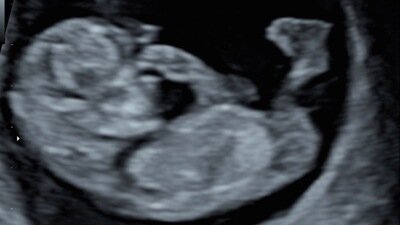

Lincolnshire midwives confuse baby’s head with bottom during routine appointments and mums don’t know their baby is breech until during labour.

It seems far too common and easy for midwives to confuse babies heads with their bottoms in low risk mothers who are not offered a presentation scan on the NHS. A third trimester scan is offered on the NHS in other counties but not in Lincolnshire.